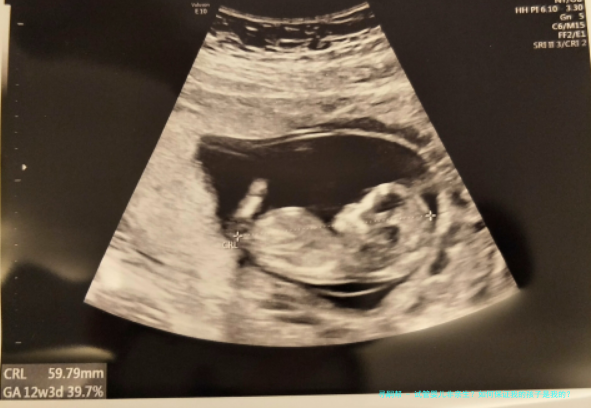

安徽“试管婴儿出生8年后被发觉放错胚胎”事件,引发注意。试管婴儿非亲生?怎么样保证我的孩子是我的?跟着人类人类辅助生殖技术的出世,给有生育困境的患者带来希望。辅助生殖技术不只是医药学技术,更是关涉到伦理问题,该怎样保障在辅助生殖技术过程顺当进行,需要从各个环节抓起,一环紧扣一环,每一步骤都至关重要。

试管婴儿技术分为第一代、第二代及第三代试管婴儿。

即是常规体外受精-胚胎移植技术(试管婴儿(IVF)-ET),是指将精子和卵子在体外培育,在卵裂期或囊胚期移植回子宫内腔着床发育。第一代试管婴儿技术主要适用于女性一方因素导致的试管助孕,优点是受孕卵中的卵子精子是当然选择,减少人造干涉。